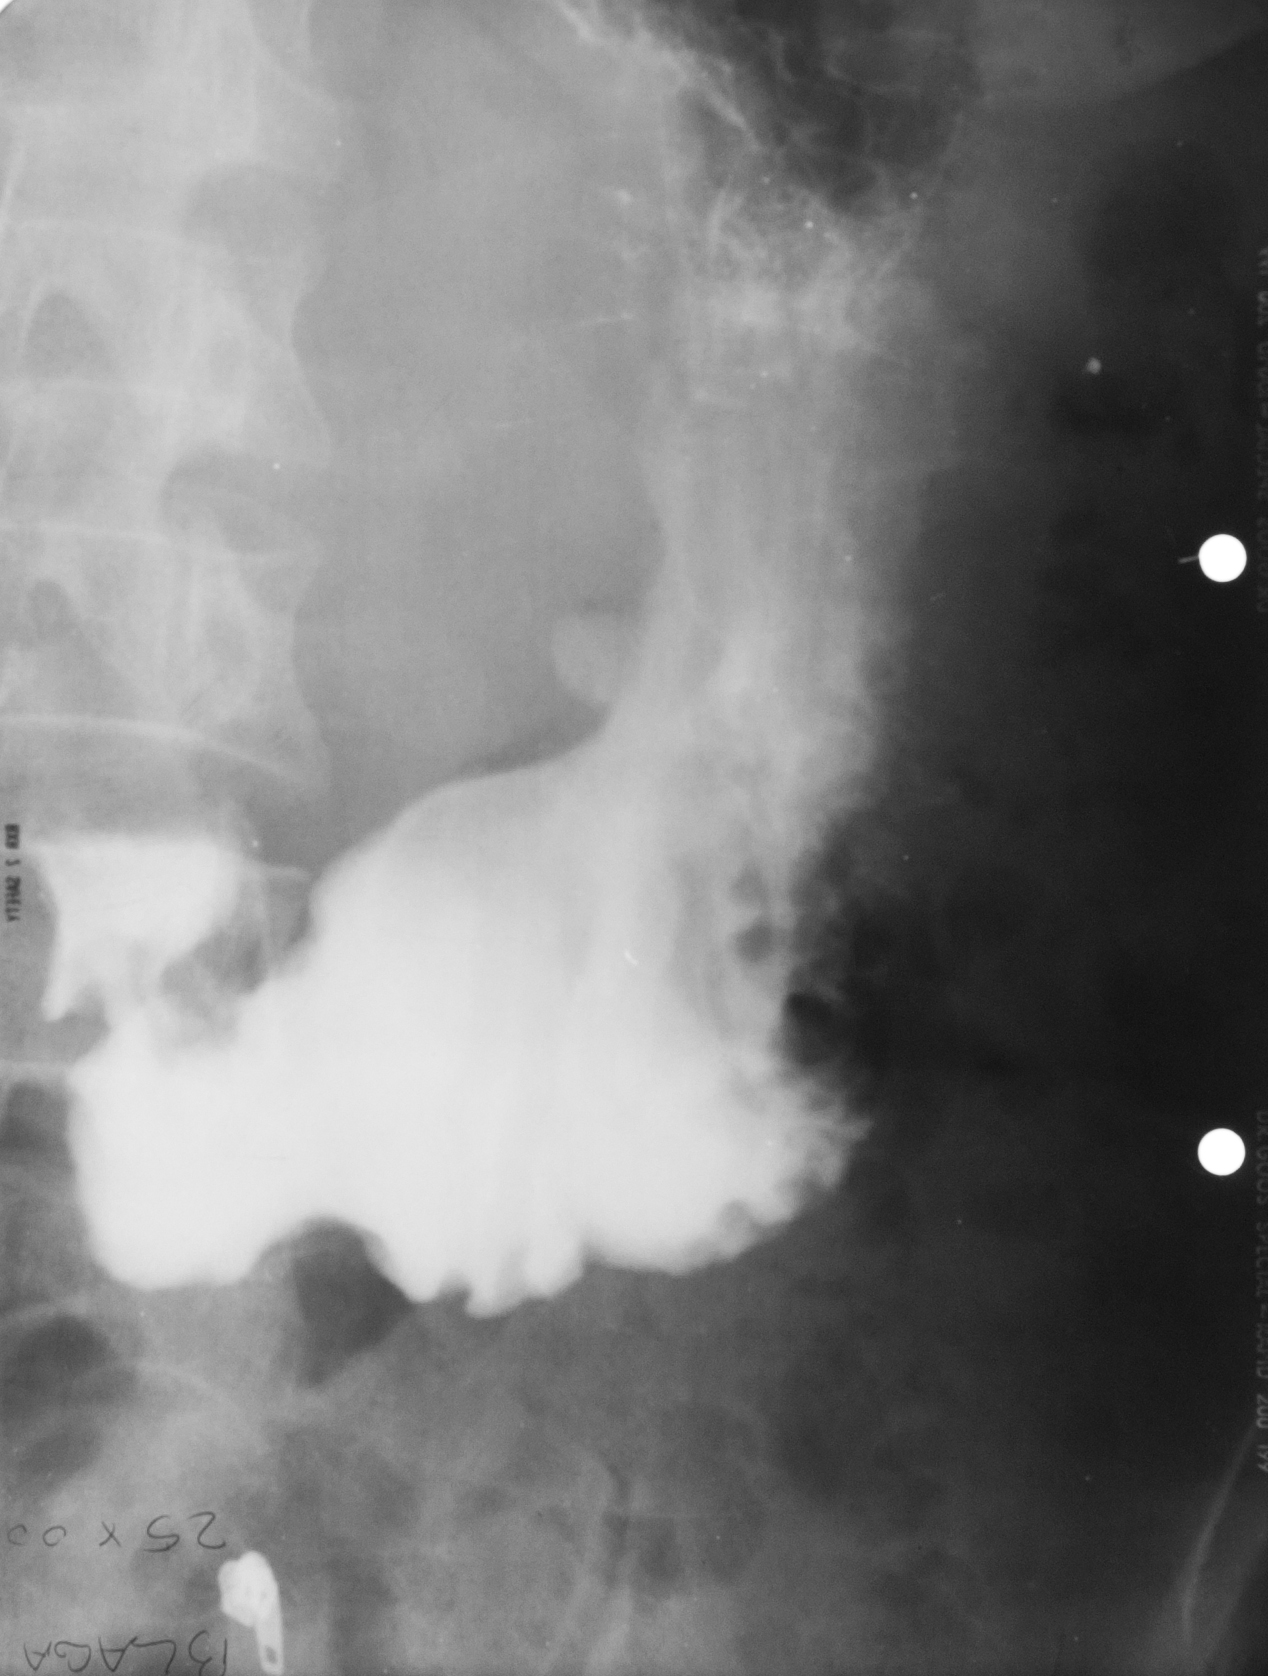

STOMAC NORMOTON(aspectul radiologic)

Tranzitul baritat al stomacului.Aspectul stomacului cu substanță de contrast:forma literei J cu fornix,corp,antru,canal piloric + bulb duodenal,D2(partea descendentă a duodenului

STOMAC ORIENTALIZAT/HIPERTON (aspect radiologic normal)

Stomacul hiperton este caracteristic persoanelor scurte și grase

STOMAC ALUNGIT (aspect radiologic normal)

Stomac alungit cu polul inferior aproape de nivelul crestei iliace.Este caracteristic persoanelor longiline

STOMAC DILATAT

Stomac destins cu substanță de contrast cu polul inferior aflat în micul bazin

Stomac dilatat cu mult lichid de secreție și stază gastrică

: NIȘA BENIGNĂ

Tranzit baritat la nivelul stomacului..La nivelul curburii mici se observă o imagine de adiție mai mult adâncă decât lată,cu pliuri de mucoasă ce converg spre zona respectivă

NIȘĂ BENIGNĂ

Nișă benignă mai mult adâncă decât lată,tot la nivelul micii curburi

ASPECT DE CLEPSIDRĂ AXIALĂ

Tranzit baritat cu aspect biloculat al corpului gastric:aspect de clepsidră axială(ceea ce înseamnă că în zona mediocorporeală se află un neoplasm infiltrativ)

ASPECT BILOCULAT AL CORPULUI GASTRIC

Tranzit baritat la nivelul corpului gastric cu incizură la nivelul curburii mari și aspect biloculat al corpului gastric:biloculare de tip benignă

Biloculare excentrică?

ASPECT BILOCULAT AL CORPULUI GASTRIC

Biloculare excentrică

NIȘĂ BENIGNĂ

Tranzit baritat la nivelul stomacului..Se observă o imagine de adiție,nișă de tip benign,mai mult adâncă decât lată

: NIȘĂ BENIGNĂ

Nișă benignă care iese din conturul gastric,mai mult adâncă decât lată

Prima imagine de la stânga:examinare în dublu contrast

A doua imagine:examinare în mono contrast

: STENOZĂ

Tranzit baritat cu stenozarea lumenului gastric la nivel corporeal și antral

Stenoză,cel mai probabil,de tip malign